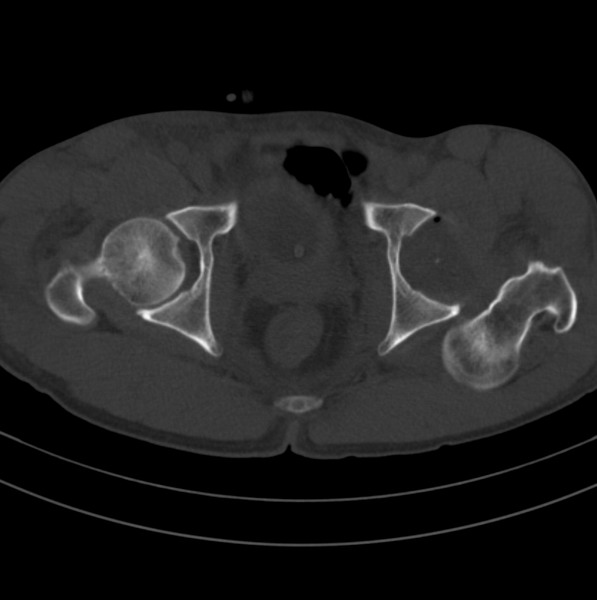

标题: CT18589:股骨头囊状阴影怎么下结论?

男、53

股骨头内的囊状阴影怎么下结论?

1.左髋后脱位。

2.囊状影考虑退变。

髋关节脱位、股骨头疝窝。

左髋关节脱位,其内圆形低密度影,考虑为股骨头疝窝

左侧髋关节后脱位;左侧股骨头疝窝。

左侧髋关节后脱位;左侧股骨头疝窝

脱位够厉害的

左侧髋关节后脱位、左侧股骨颈疝窝。